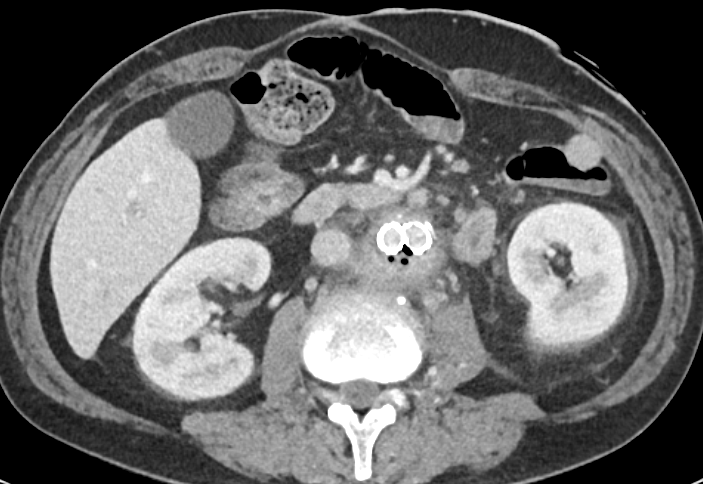

✨Up Next in our Member Spotlight Series - featuring Dr. Rocky Saenz! His passion for education has inspired numerous medical students and radiology residents. Dr. Saenz has made significant strides for DOs and radiologists, enhancing their recognition in the medical field.